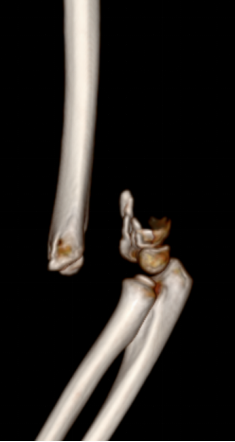

1、小红(化名):女、6岁、吊单杠时不慎摔伤致左肘部肿痛、畸形、活动受限2小时就诊我院。(下图为患儿术前X线片及CT检查)

此种类型的骨折称为肱骨髁上骨折,在完善相关辅助检查后予行麻醉下平乐郭氏手法正骨经皮钢针内固定治疗,术后患儿恢复良好,手术部位只有几个小针眼。(下图为患儿术后X线片)